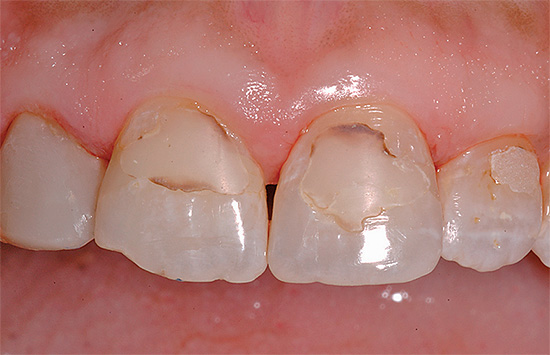

E in questa foto - carie profonde, che già minaccia di svilupparsi in pulpite:

Con la carie profonda, come suggerisce il nome, gli strati profondi di dentina sono interessati fino alle aree vicino alla polpa. Se la polpa stessa è interessata, la pulite inizia con dolore acuto e il rischio di infiammazione parodontale.

A seconda del luogo di manifestazione, la carie profonda sembra diversa. Ad esempio, nella foto sotto - una lesione dentale piuttosto significativa con carie cervicale: